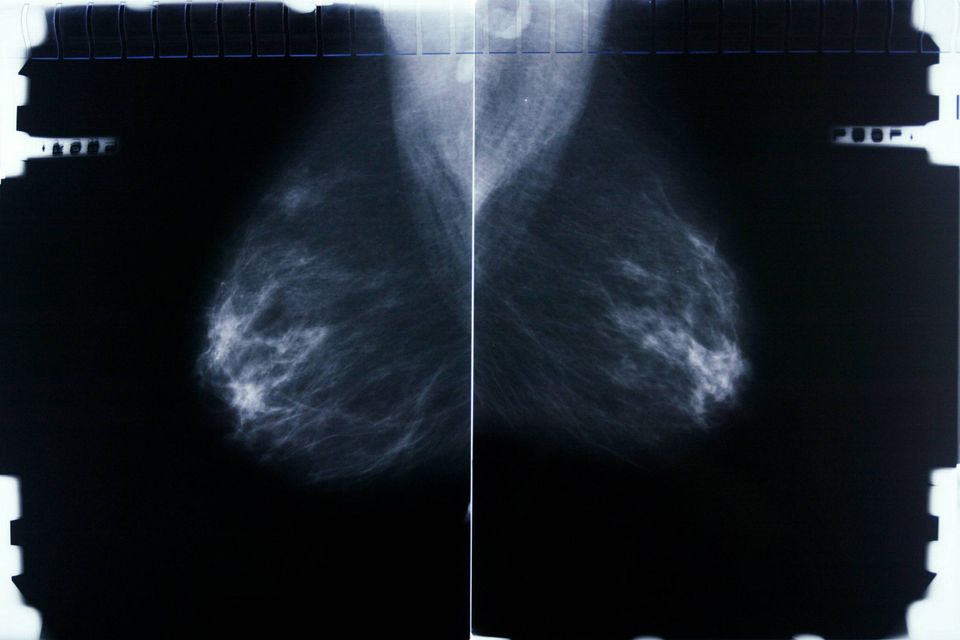

Knap 300 kvinder med brystkræft opfordres til at søge erstatning

Screeningspukkel smitter af på ventetiden på brystkræftbehandlingen i Region Hovedstaden.

Ventetid på kræftscreening har ført til problemer med at behandle de kræftsyge til tiden. Ikke mindst i Region Hovedstaden.

Det viser en orientering, som sundhedsminister Sophie Løhde (V) har givet til Folketingets Sundhedsudvalg om de langvarige problemer, Region Hovedstaden har haft med at overholde kravet om, at der højest må gå 2 år og 3 måneder mellem, at kvinder bliver screenet for brystkræft. Mange kvinder har ventet mere end et halvt år længere, end de ifølge loven burde på at få tjekket deres bryster for tegn på kræftknuder.

For 279 kvinder kan den forlængede ventetid have haft meget alvorlige konsekvenser.